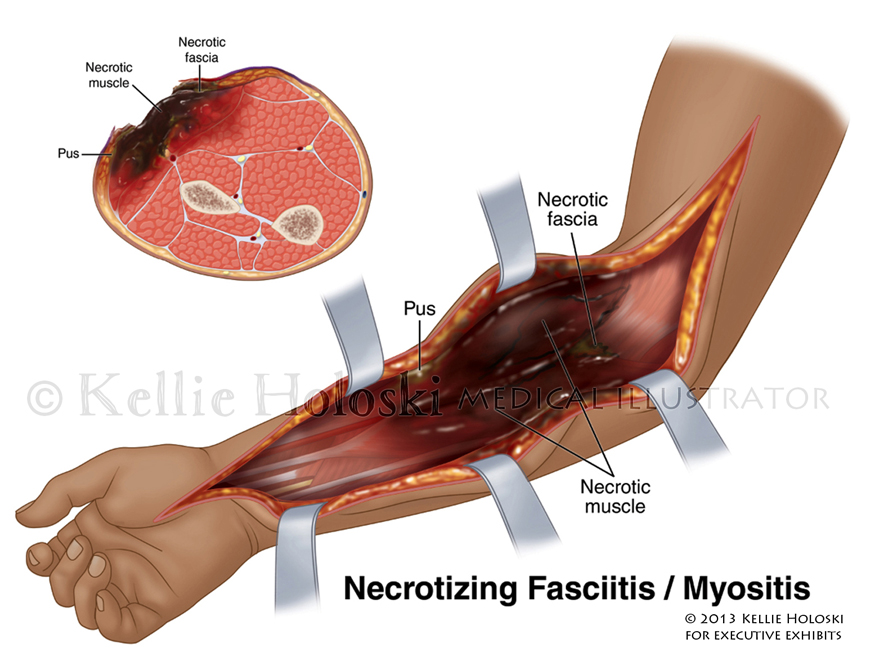

Fasciitis and Myositis,

Adobe Photoshop

Courtroom exhibit for Executive Exhibits;

©Kellie Holoski -